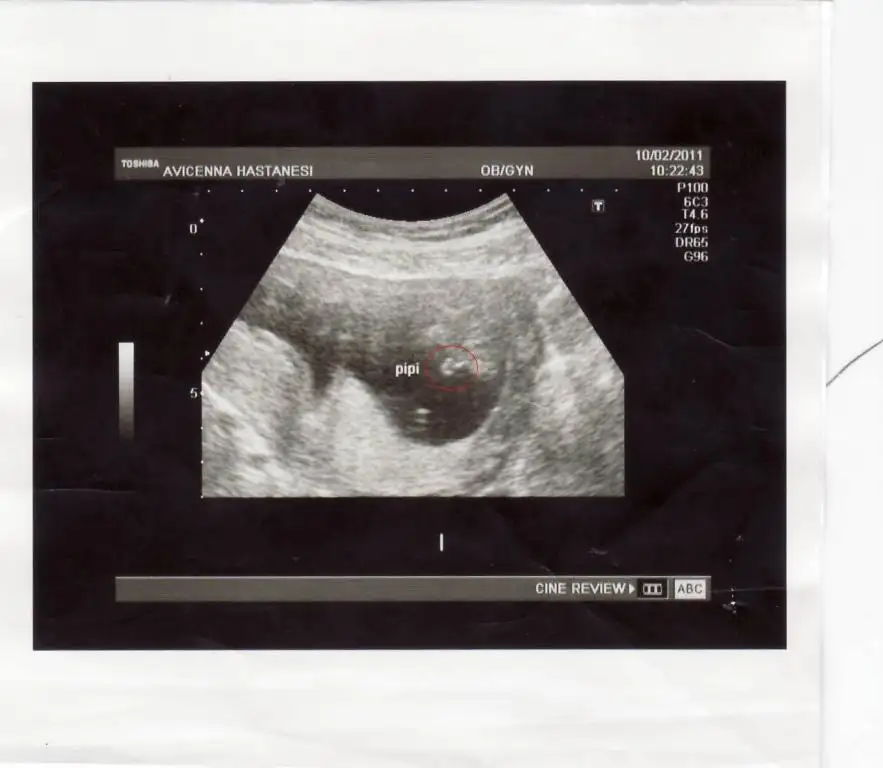

bacaklarını açmıştı oğlum doktor teyzeside böyle çekti işte

kırmızı yuvarlak içine aldım

maişllh maşlhhh yerim onun pipisiiniiiEki Görüntüle 142791

iyi akşamlar hanımlar nasılsınz?ben bi kaçgündür çok kötüydüm bugün yine fenalaşınca dr gittim ve drum bana hiçde iç açıcı konuşmadı çok üzüldüm ağladımm,sonra eşimi aradım doğum yaptığım özel hastaneye gittim ordaki drum muayene edip ultrasona soktu ve gayet sağlıklı olduğunu ve hatta gününden de önde gittiğini söyledi çok mutlu olduk,e tabi sancılarımıda tesbit etti ultrasonda çok gelişmiş bir hastane çünkü,ilaç verdi onu içince rahatlicam inş,tek dozluk bu gece verdi içince hemen uyu ve 3saat hiç wc ye gitmiceksin dedi,diğerleride hergün 1tane dedi,zaten senin 2 çocuğunda iri oldukları için buda iri olucak maşallah dedi,veeeeeeeeeeeeeeeeeeeeeeeeeeee bir oğlum olucağınıda söyledi,zaten hemen cihazı karnıma tutunca pipiyi gördük rabbim umarım sağlıklı hamilelik geçirip kucağımıza alıp doyaaa doya severiz..